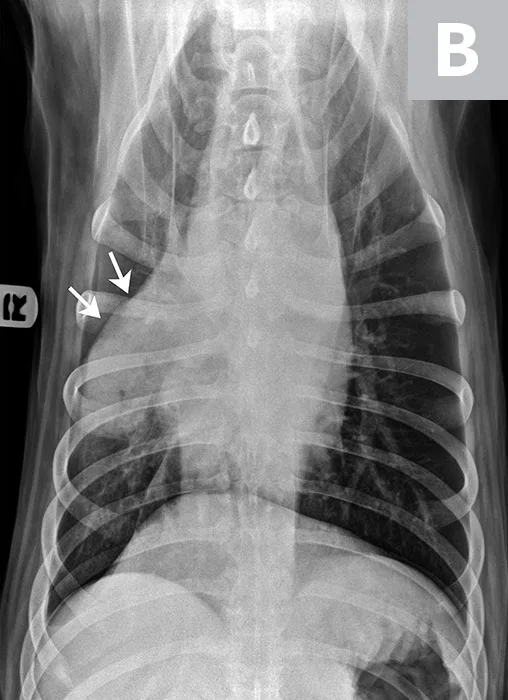

FIGURE 1

Fine-needle aspirate of a cranial mediastinal mass in a 10-year-old spayed schnauzer. Peripheral blood surrounds several irregularly shaped cells with abundant vacuolated cytoplasm and round to irregularly shaped nuclei of variable size (moderate to marked anisokaryosis). These nuclei exhibit finely to coarsely stippled chromatin and occasional prominent nucleoli of variable shapes and sizes. The largest cell is binucleated (arrow), which is a common feature of histiocytic sarcoma.